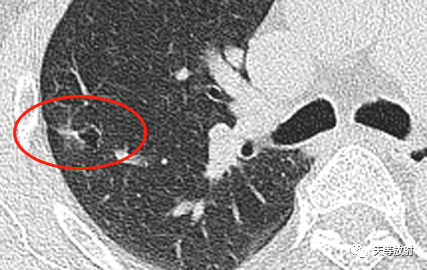

27c1b637ca1e79bb0691e64b16e95d9b.png

这个层面出现囊腔+实性结节,囊壁较厚。